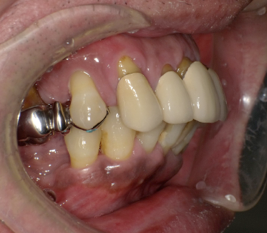

術直後の写真です

オールオン6本のインプラントをいれました

初期固定もよかったので即時荷重をおこなっています

術後2週間 傷もきれいに治ってきています